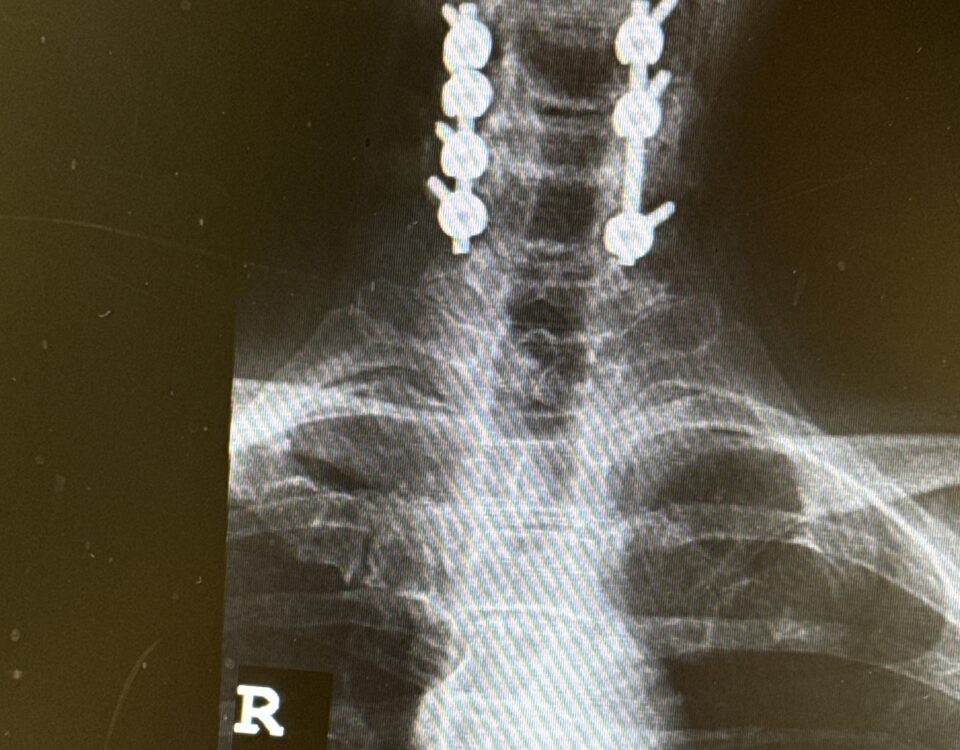

Patients may require an occipital-cervical fusion for both cranio-cervical and atlanto-axial instability, depending on the anatomy. Patients who have long segment posterior cervical fusions can sometimes […]

I specialize in and am very familiar with patients who have osteoporosis and require spinal surgery for degenerative […]